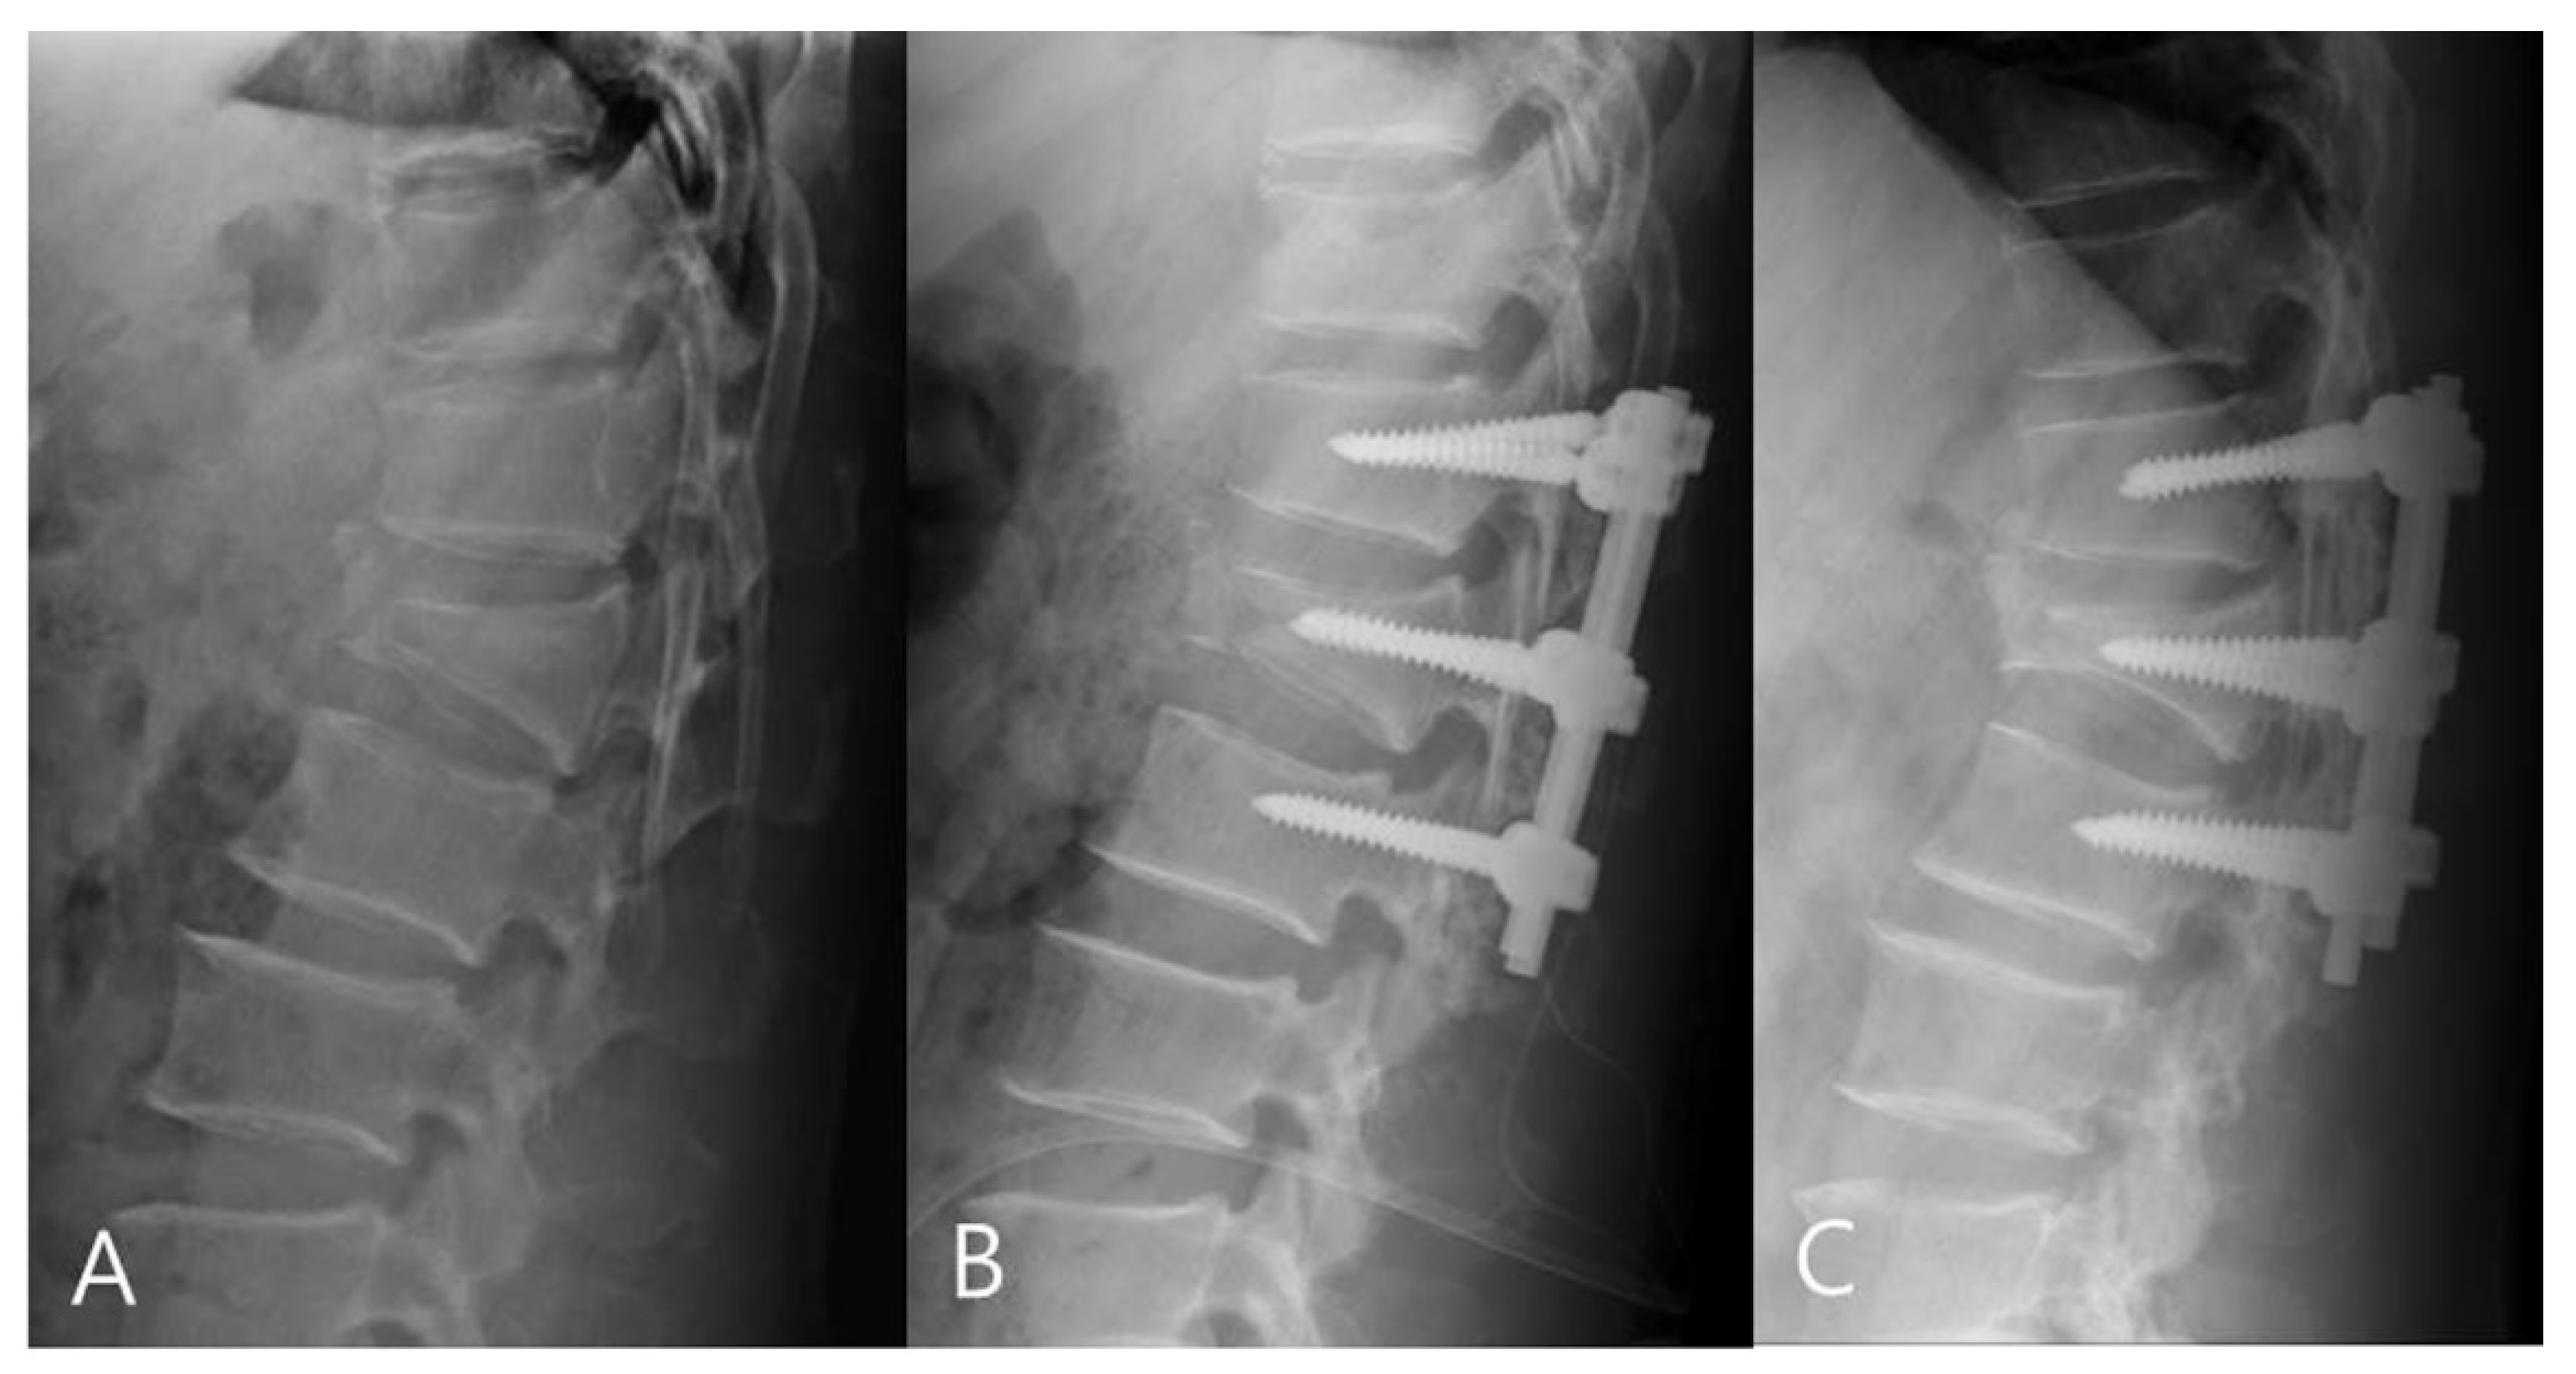

Radiographic evaluations were based on anteroposterior (AP) and lateral views, flexion and extension lateral views, and three-dimensional CT scans. Using the ratio of the heights of the anterior and posterior vertebral wall (on lateral views of the injured vertebral body), we calculated the sagittal index (SI) preoperatively, immediately after surgery, and at the final follow-up (Figure 1). Kyphotic deformity was evaluated on lateral views using the Cobb method. Regional kyphosis angle (RKA) between the superior endplate of the vertebra above the apical (injured) vertebra and the inferior endplate of the apical vertebra below were measured preoperatively, immediately after surgery, and at the final follow-up (Figure 1).

Figure 1.

(A) Sagittal index (SI) was calculated by the ratio of the heights of the anterior and posterior vertebral wall. (B) Regional kyphosis angle (RKA) was measured on lateral radiographs using the Cobb method. RKA between the superior endplate of the vertebra above the fractured vertebra and the inferior endplate of the vertebra below the fractured vertebra were measured.